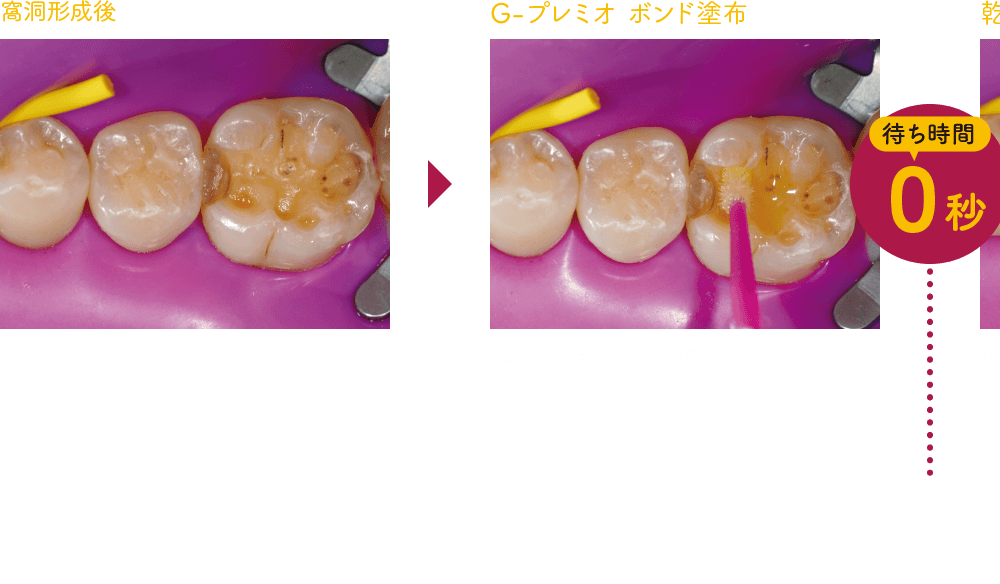

塗布後の待ち時間 「0秒」の簡便性

ボンディング材塗布後、待ち時間なしで乾燥、光照射へとスピーディにおこなえ、特に唾液の多い下顎臼歯部や小児、高齢者の症例等にもストレスなくコンポジットレジン修復がおこなえます。

基本ステップ(コンポジットレジン修復)